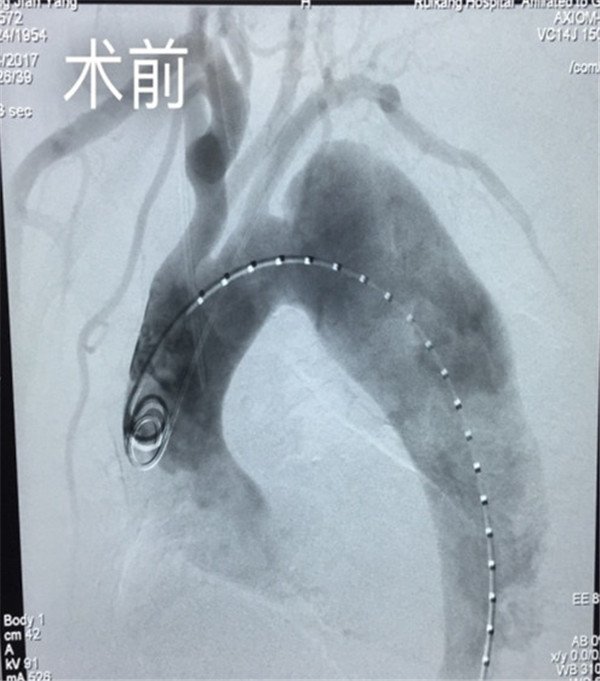

• 心血管内科一区争分夺秒救回频发心脏骤停的“镜面人”

心血管内科一区争分夺秒救回频发心脏骤停的“镜面人”

2016年4月22日凌晨,一位特殊镜面病人转入我院心血管内科一区,顿时让这个夜班变得忙碌而又与众不同。 镜面人,又称镜子人或镜像人,即心...

发布时间:2016-04-25 来源: